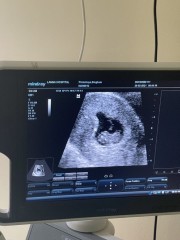

ไปซาวมาแล้วอายุครรภ์6วีค แต่ยังไม่เห็นตัวและหัวใจน้องเลยคะ อยากถามแม่ๆบ้านอื่นเจอน้องกับหัวใจตอนกี่วีคคะ มีใครเจอช้ากว่า6วีคมั้ยคะ (หมอบอกให้ทำใจเผื่อไว้ อาจจะท้องลม) :(

บ้านนี้ซาวน์ตอน6วีค5วันค่ะ ซาวน์หน้าท้องไม่เห็นอะไรเลยค่ะ คุณหมอเลยซาวน์ช่องคลอดเจอน้องจิ๋วมากเลยค่ะ และวัดอัตราการเต้นของหัวใจตอนนั้น130ครั้ง/นาทีค่ะ ซาวน์ครั้งหน้าขอให้คุณแม่เจอน้องนะคะ